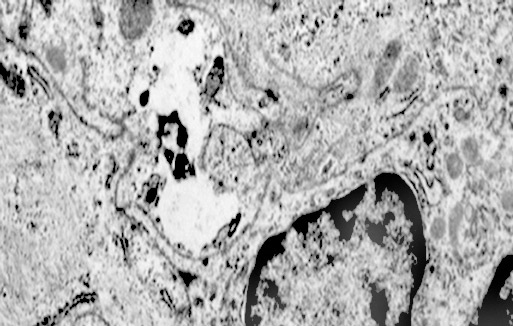

2/b AUTOLISOSOMA

Alcune cellule meningoteliali sono sedi, sopratutto a livello delle fasce periferiche, di ampie vescicole, di forma irregolare le quali sono demarcate da una membrana a mono-strato; gli spazi di queste vescicole sono in buona parte occupati da materiale amorfo, da frammenti filamentosi e da organuli intracitoplasmatici,tutto sottoposto a degradazione.

E’ possibile anche il reperto di elementi cellulari aventi il citoplasma occupato da ampie vescicole,delimitate da una membrana a monostrato, le quali sono ricolme di materiale amorfo,da strutture granulo-filamentose o da frammenti di organuli.

Non è raro il riscontro di cellule meningoteliali le quali hanno il citoplasma in buona parte occupato da una formazione cava,irregolarmente rotondeggiante; questa è delimitata da una spessa membrana ed è occupata da frammenti di citoplasma e da singoli organuli,tutto in corso di degradazione.

Nel contesto di alcune cellule coese,tutte contenenti focolai di micro e macroautofagia,è possibile rintracciare una di esse la quale è occupata da una ampia vescicola,a pareti frastagliate e lacerate, quasi ricolma di organuli e materiale filamentoso. Il citosol di tutte queste cellule è iperchiaro e gli organuli ivi contenuti sono in numero esiguo e mostrano segni morfologici di necrobiosi.